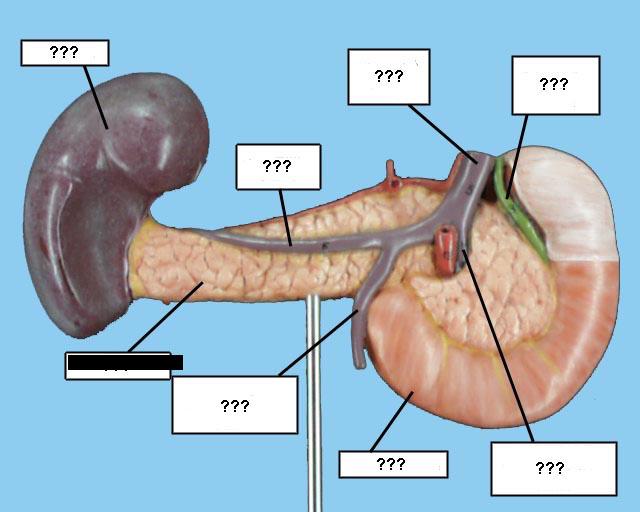

(Common) Hepatic Duct

Common bile duct

Common hepatic artery

Cystic duct

Duodenum

Gall bladder

Hepatic portal vein

Kidney

Liver

Pancreas

Pancreatic duct

Splenic artery/vein

Stomach